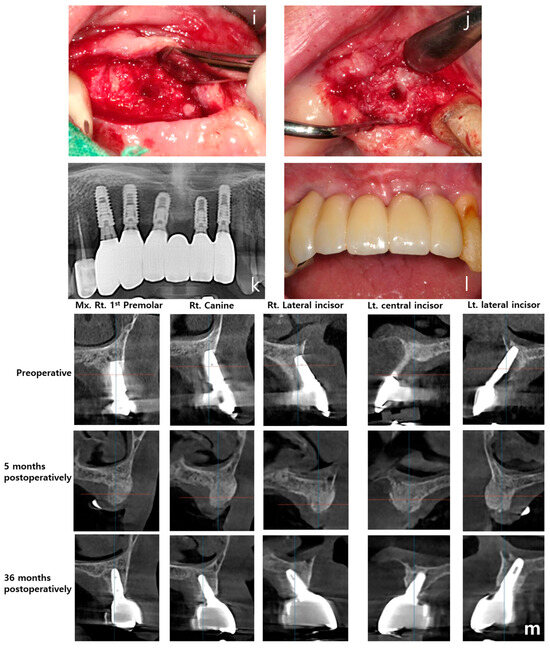

Clinical Application of rhBMP-2 and Three-Dimensinal Preformed Titanium Mesh with Allograft and Xenograft for Peri-Implant Horizontal and Vertical Bone Augmentation–A Narrative Review with Technical Report

2. Materials and Methods

3. Results

- Clinical efficacy: the combination of rhBMP-2 and a 3D-preformed titanium mesh (3D-PFTM) proved effective for reconstructing severely resorbed alveolar bone;

- Structural stability: the use of 3D-PFTM, particularly the OssBuilder system, provided reliable structural support for bone regeneration;

- Implant success: the combined approach resulted in stable bone regeneration and long-term implant success;

- Therapeutic value: the so called BOXAM (BMP-2, Oss-builder, xenograft, allograft, maintenance) technique appears to be a promising and reproducible strategy in dental and maxillofacial surgery.